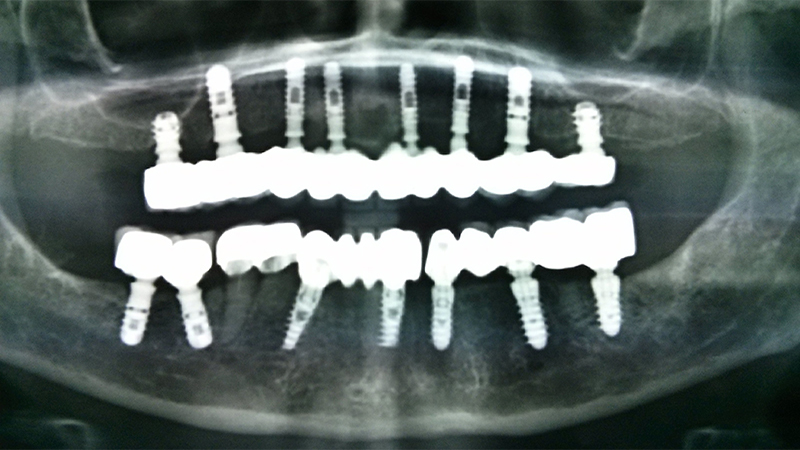

All on 4 Implants

All on 6 Implants

All on 8 Implants

FULL MOUTH REHABILITATION with IMPLANTS